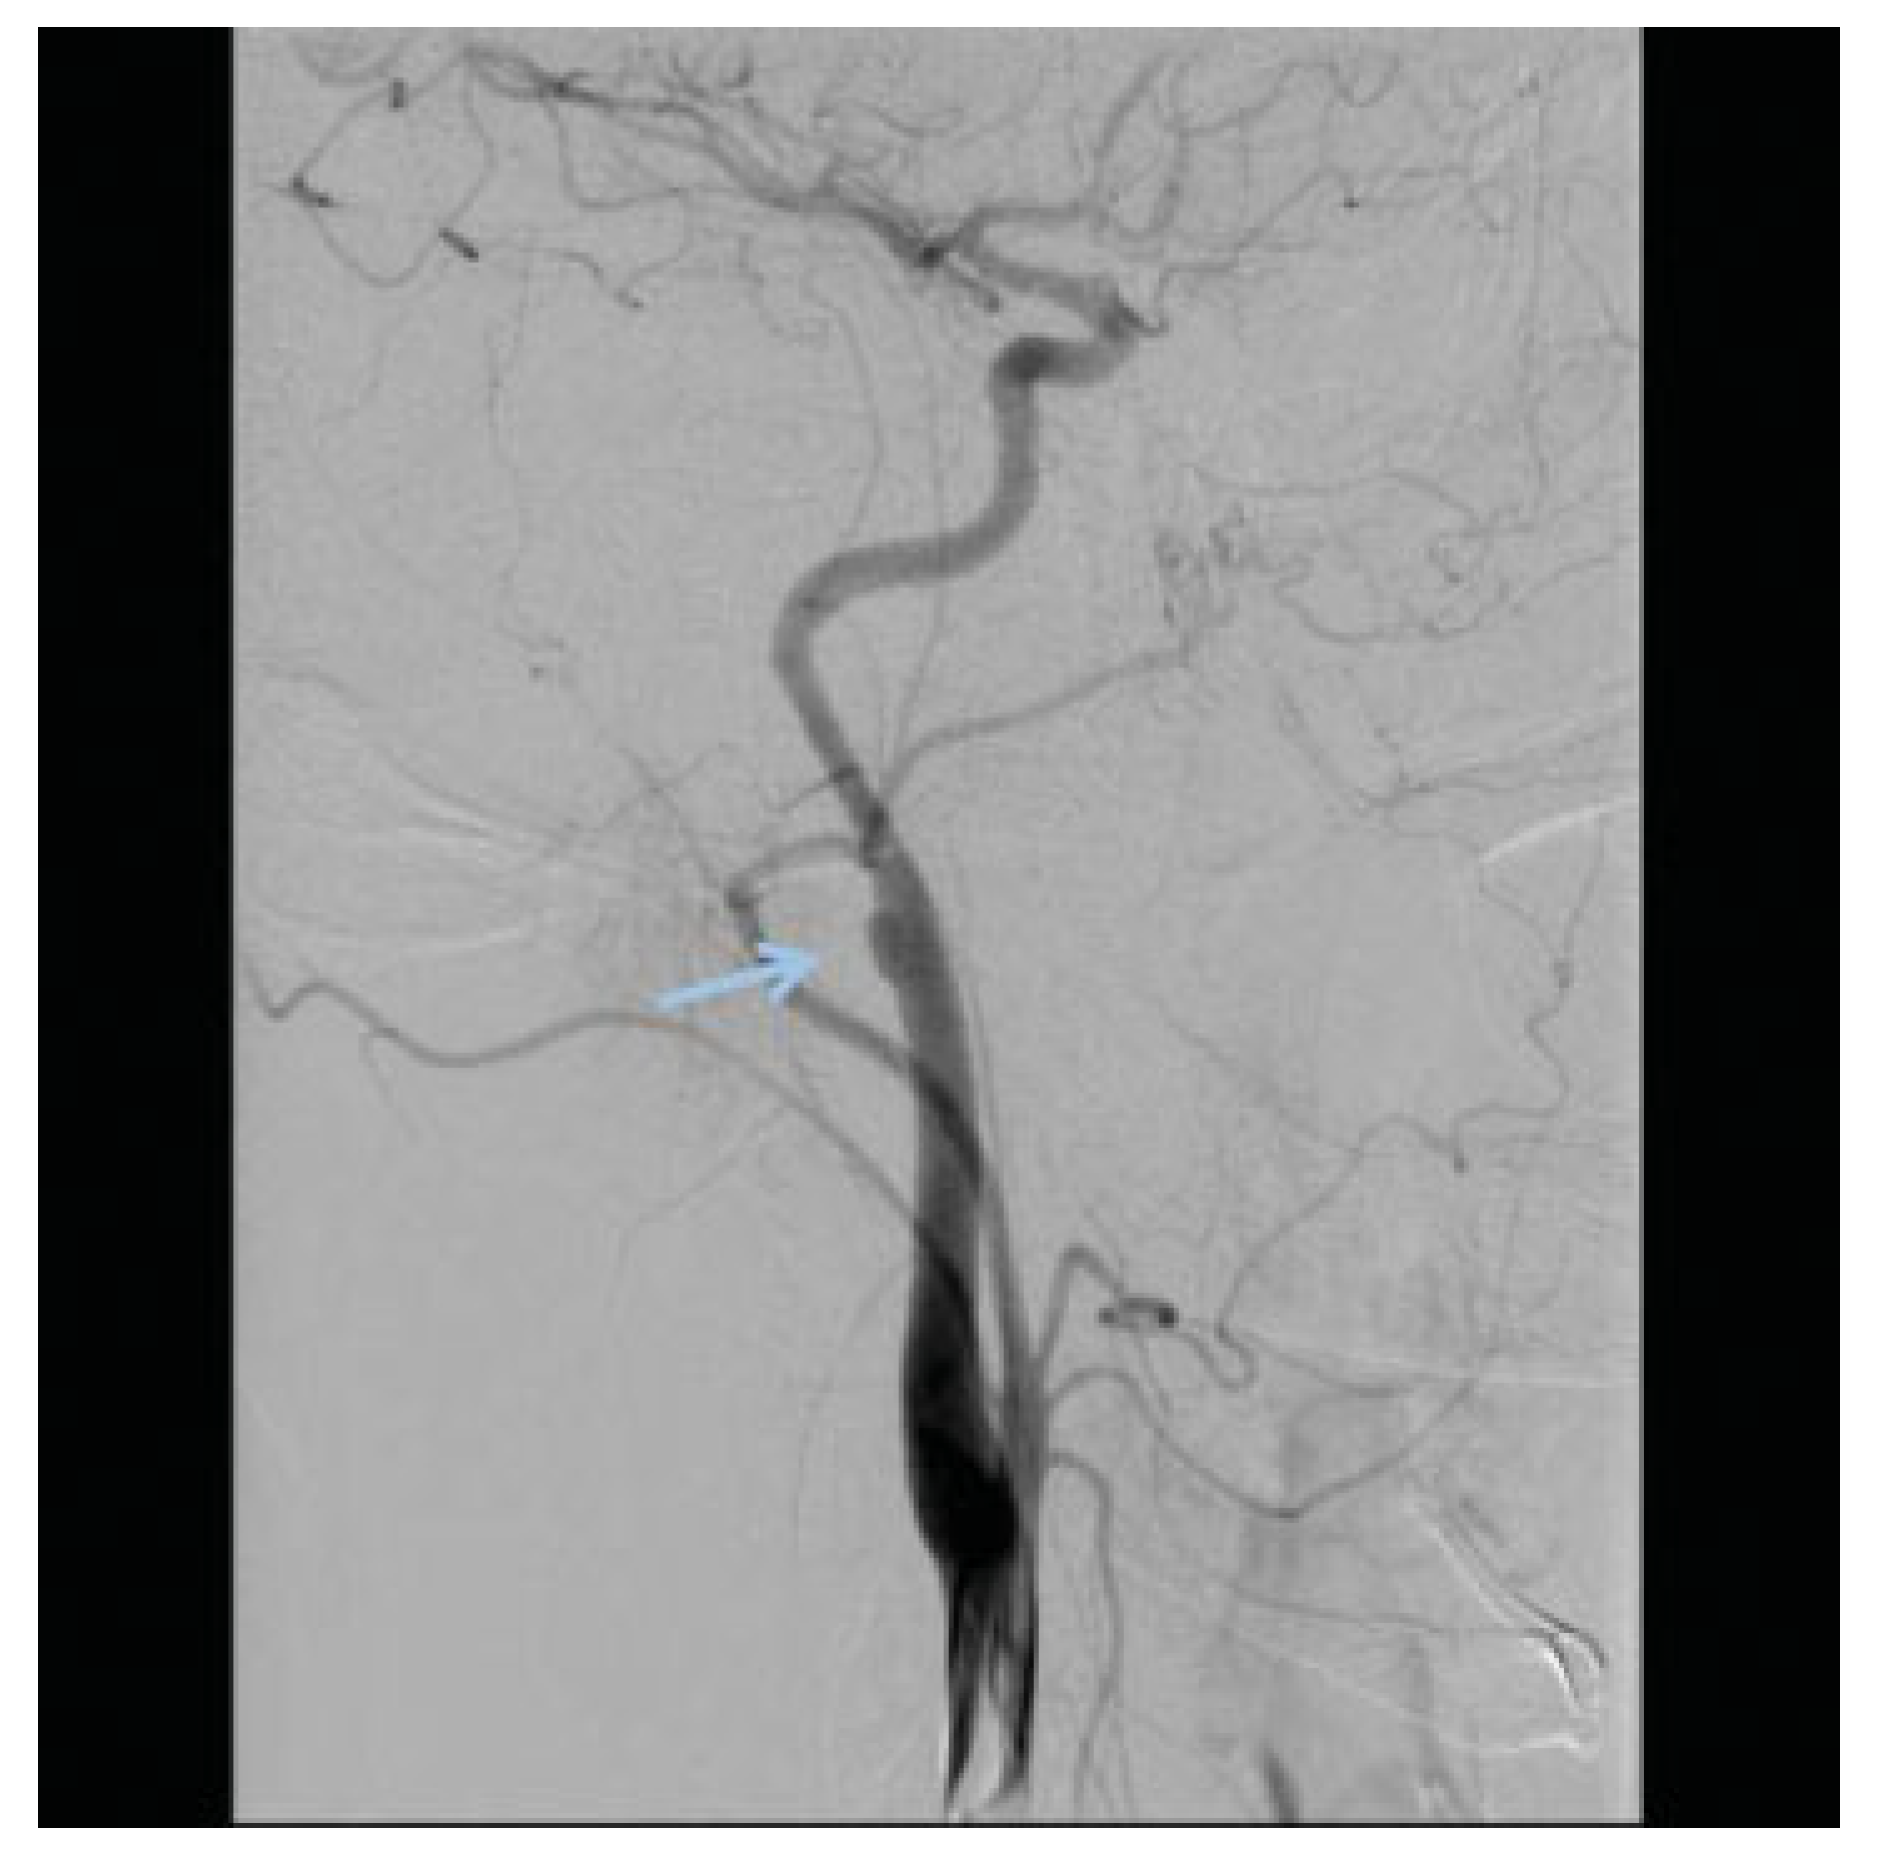

Penetrating Extracranial Carotid Artery Trauma

Intracranial Carotid Artery Trauma